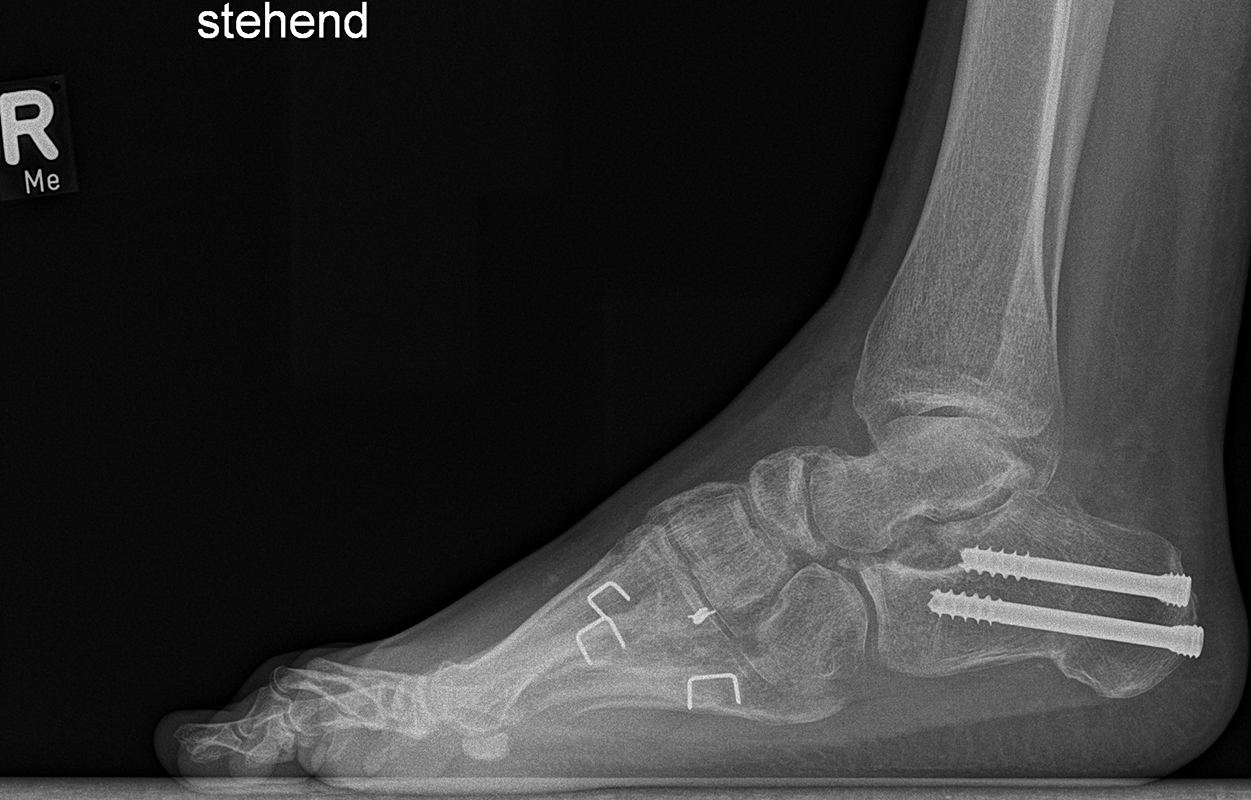

Knick-Senk-Platt-Fuß Korrektur mit dem Canalis Tarsi Spacer

In der Korrektur des schmerzhaften, aber flexiblen Knick-Senk-Fußes oder Plattfußes ist die Schraubenarthrorise mit einem Sinus tarsi oder besser bezeichnet als Canalis tarsi Spacer und alternativ mit einer Calcaneus-Stopp-Schraube seit vielen Jahren ein etabliertes Verfahren und führt zu einer kompletten Korrektur von flexiblen Knick- und Plattfuß-Fehlstellungen (Abb. 7). Die nötige Schnittlänge über dem Sinus tarsi beträgt für beide Verfahren 1 cm.

Abb. 7 a-e: Knick-Senk-Fuß prä- und postoperative Situation (a-b), ventrale und dorsale Ansicht (c-d). Laterale Ansicht des Hautschnittes über dem Sinus tarsi (e).

Zum Lesen der Bildbeschreibung und zur Vollansicht bitte die Bilder anklicken. Bilder: A. Helmers.